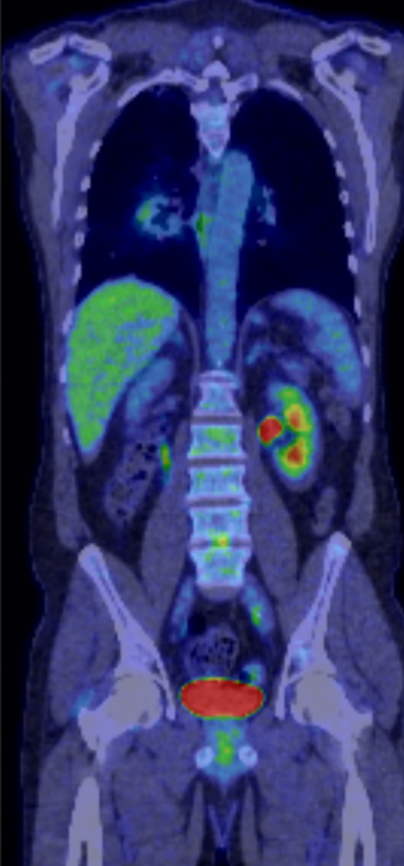

3. Lumbar Discitis